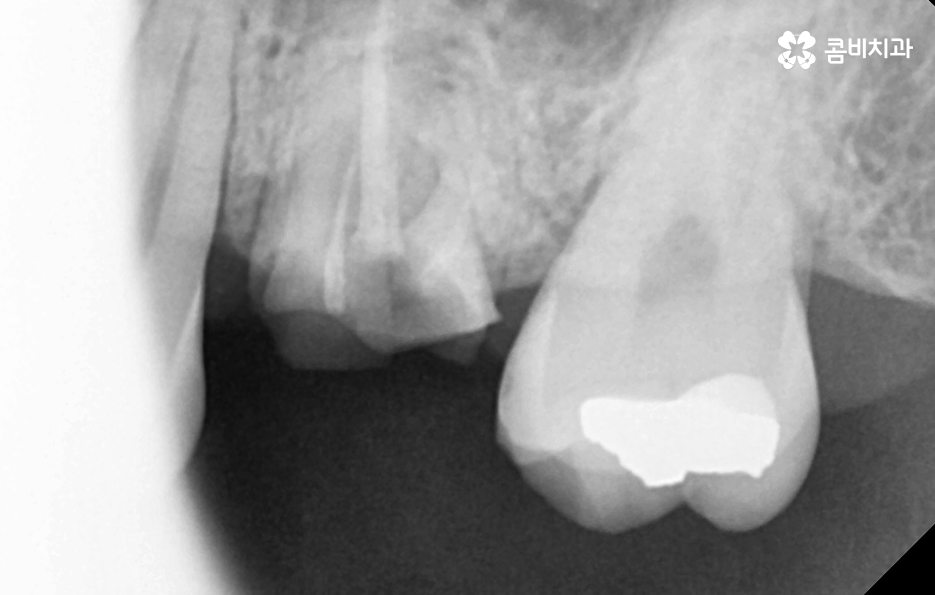

보통 뿌리 끝에 발생한 염증이나 고름의 경우 엑스레이 등의 검사를 통해 발견된 문제로 신경치료가 필요한 케이스인데 환자분의 입장에서는 당장 불편함을 크게 못 느끼고 신경치료를 하려면 치과에 여러 번 방문해야 하기 때문에 치료를 미루는 경우도 많이 있어요.

뿌리 끝에 발생한 염증의 경우 불편함을 못느끼더라도 빨리 치료하는 것이 좋은 이유는 시간이 지날수록 작았던 염증은 점점 커지게 되고 잇몸 뼈를 녹게 만들어 치아가 결국 흔들리게 될 수 있고, 당장 통증이 없더라도 치료 시기를 놓쳐, 일정 수준 이상으로 진행이 된 경우 급성치수염 증상으로 진통제를 먹어도 통증이 잡히지 않을 정도로 극심한 통증이 동반될 수 있습니다.

잇몸 뼈에 문제가 생겨 치아가 흔들리게 되면 보통 치료의 골든타임을 놓치게 되기 때문에 이때는 신경치료를 시도할 수도 없고, 치근단절제술이나 치아재식술을 시도해 볼 수 있지만, 성공 확률이 높지 않기 때문에 치아를 발치해야 하는 경우가 대부분이라고 할 수 있어요